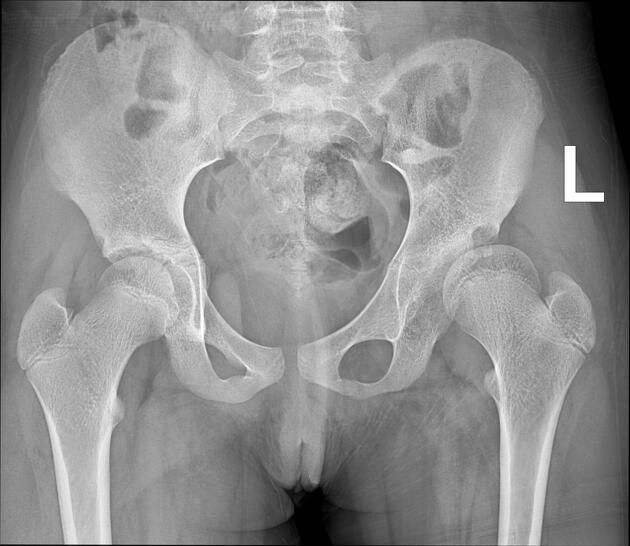

Q.12. What's the finding on X ray?

Correct Answer : B